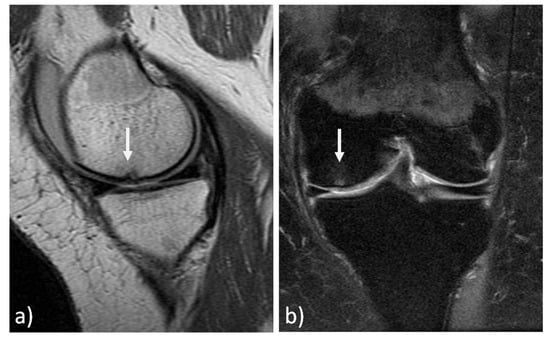

The MRI findings of 30 knees (15 mosaicplasty and 15 MACT), analyzed with the MOCART 2.0 scoring system, showed a high rate of cartilage defect filling in both groups, and a complete integration into the adjacent cartilage in half of the patients in both groups. However, the surface of the repair tissue was damaged in the majority of cases. The structure of the repair tissue was homogeneous in most cases, and the signal intensity was normal (isointense) in half of the patients in both groups. At subchondral bone level, a bony defect or bony overgrowth was reported in the majority of patients, while an edema-like marrow signal was reported in almost half of the patients in both groups (Figure 3 and Figure 4). No significant differences were reported between the two groups in the overall MOCART 2.0 scores and in all the seven subscales (Table 2).

Figure 4. MRI evaluation at 9 years’ follow-up of a medial femoral condyle lesion treated with matrix-assisted autologous chondrocyte transplantation in a 39-year-old woman. Sagittal 3D "Cube" PD (a) and coronal PD FAT SAT (b) demonstrate a good filling of the defect (arrows) and integration into adjacent cartilage, a homogeneous structure and a normal signal intensity of the repair tissue. Moreover, no significant bony defect, bony overgrowth, or major subchondral changes were detected.